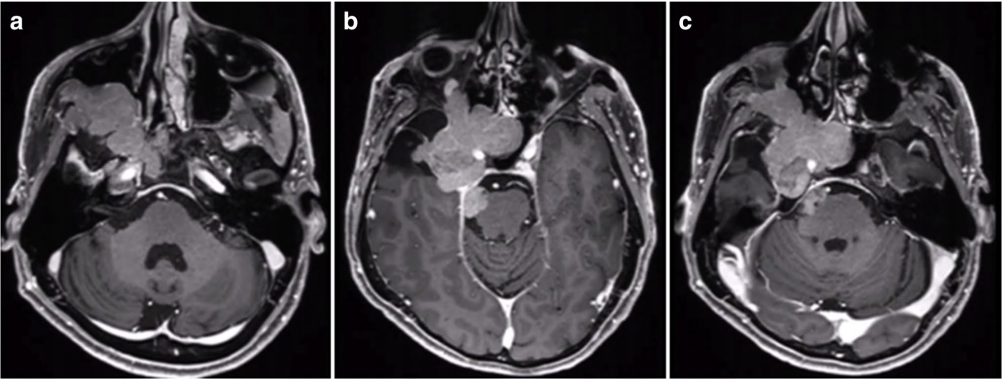

53岁男性患者,7年前在外院手术切除2级脑膜瘤。因出现三叉神经V1、V2区麻木,V3感觉迟钝入院。MRI见巨大脑膜瘤复发侵犯右侧海绵窦、眶顶、蝶窦、翼腭窝和颞后窝并通过Meckel’s腔(MC)延伸至桥小脑角(CPA)区(图a-c)。

福教授团队采用原额颞入路,显微镜+神经内镜-“双镜联合”,术后MRI显示肿瘤全切除。